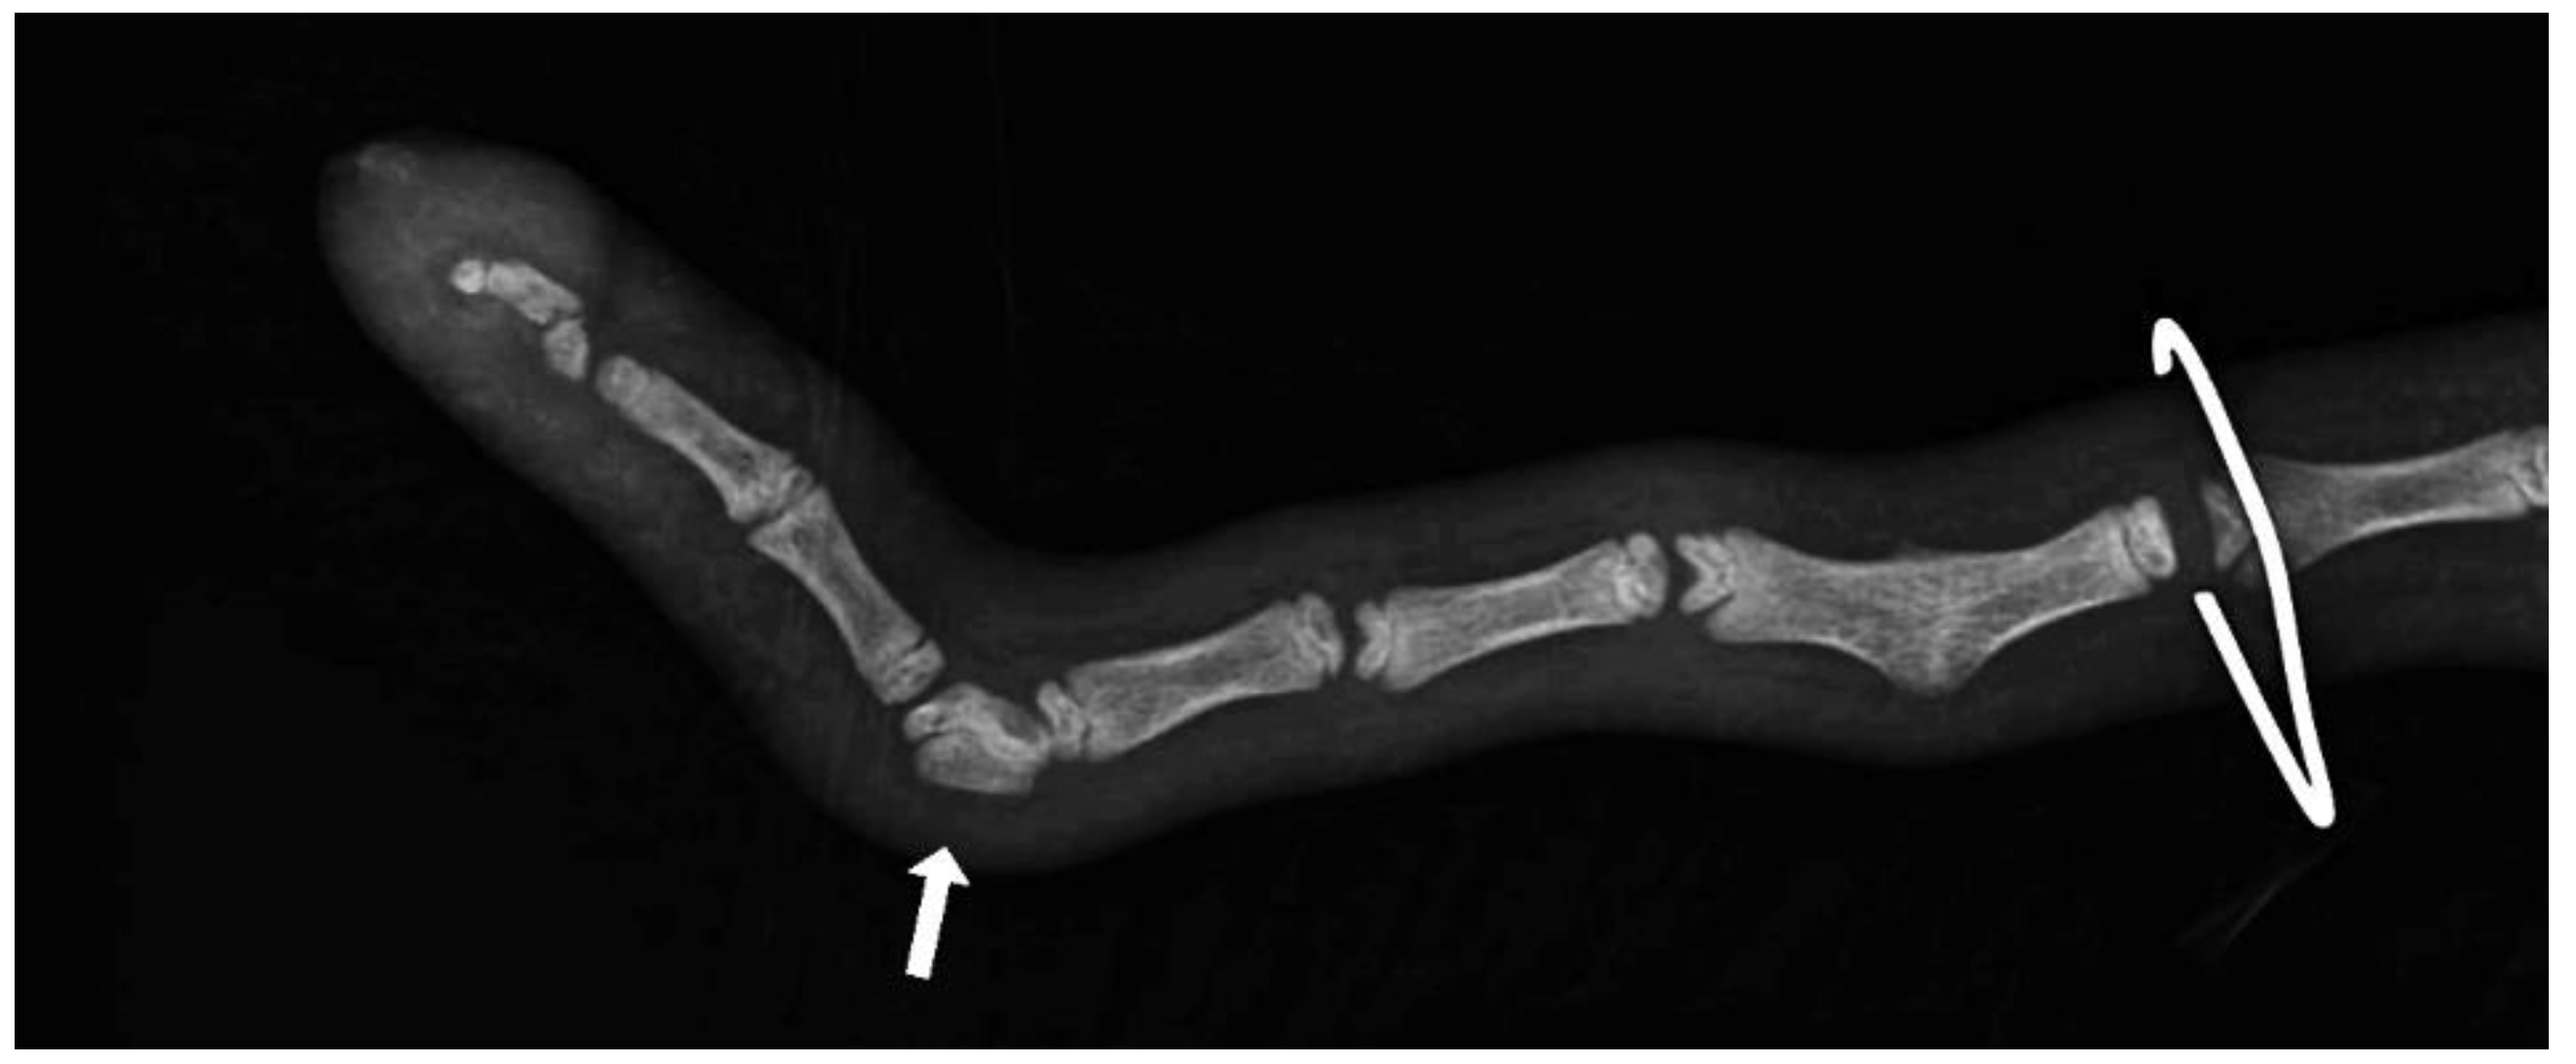

Axial deviation was defined as any manually irreparable deviation of the tail from the medians (Figure 1). A block vertebra was considered present if the vertebral boundaries of adjacent vertebrae were not clearly visible or were completely fused (Figure 2). Wedge-shaped bony structures present between two vertebrae were recorded as wedged vertebrae (Figure 3). A fracture was noted in any event where a vertebra demonstrated an interruption of bone structure (Figure 4).

Figure 4. Section of an X-ray of a lamb’s tail with fractured vertebrae.

The mean number of tail vertebrae in the Merinoland sheep population was 20.4 (±1.6) vertebrae. The mean tail length at 14 weeks of life was 41.6 cm (±4.3 cm) and mean tail circumference measured at the same time was 13.15 cm (±1.3 cm). In 33 animals (15.28%), an axial deviation of the tail spine was detected. Radiographic examination revealed various spinal lesions, such as fractures (Figure 4), wedged vertebrae (Figure 3), and block vertebrae (Figure 2). In the caudal spine, at least one block vertebra was found in 28 animals (12.96%) and at least one wedged vertebra was detected in 18 animals (8.33%). A total of 59 animals (27.51%) exhibited at least one vertebral fracture within the caudal spine. In 51 of these 59 animals (86.4%), the fracture localisation was limited to the caudal third of the tail. Six animals (10.2%) had fractures in the middle third of the tail and two animals (3.4%) had vertebral fractures in both the middle and caudal third of the tail (Table 1).